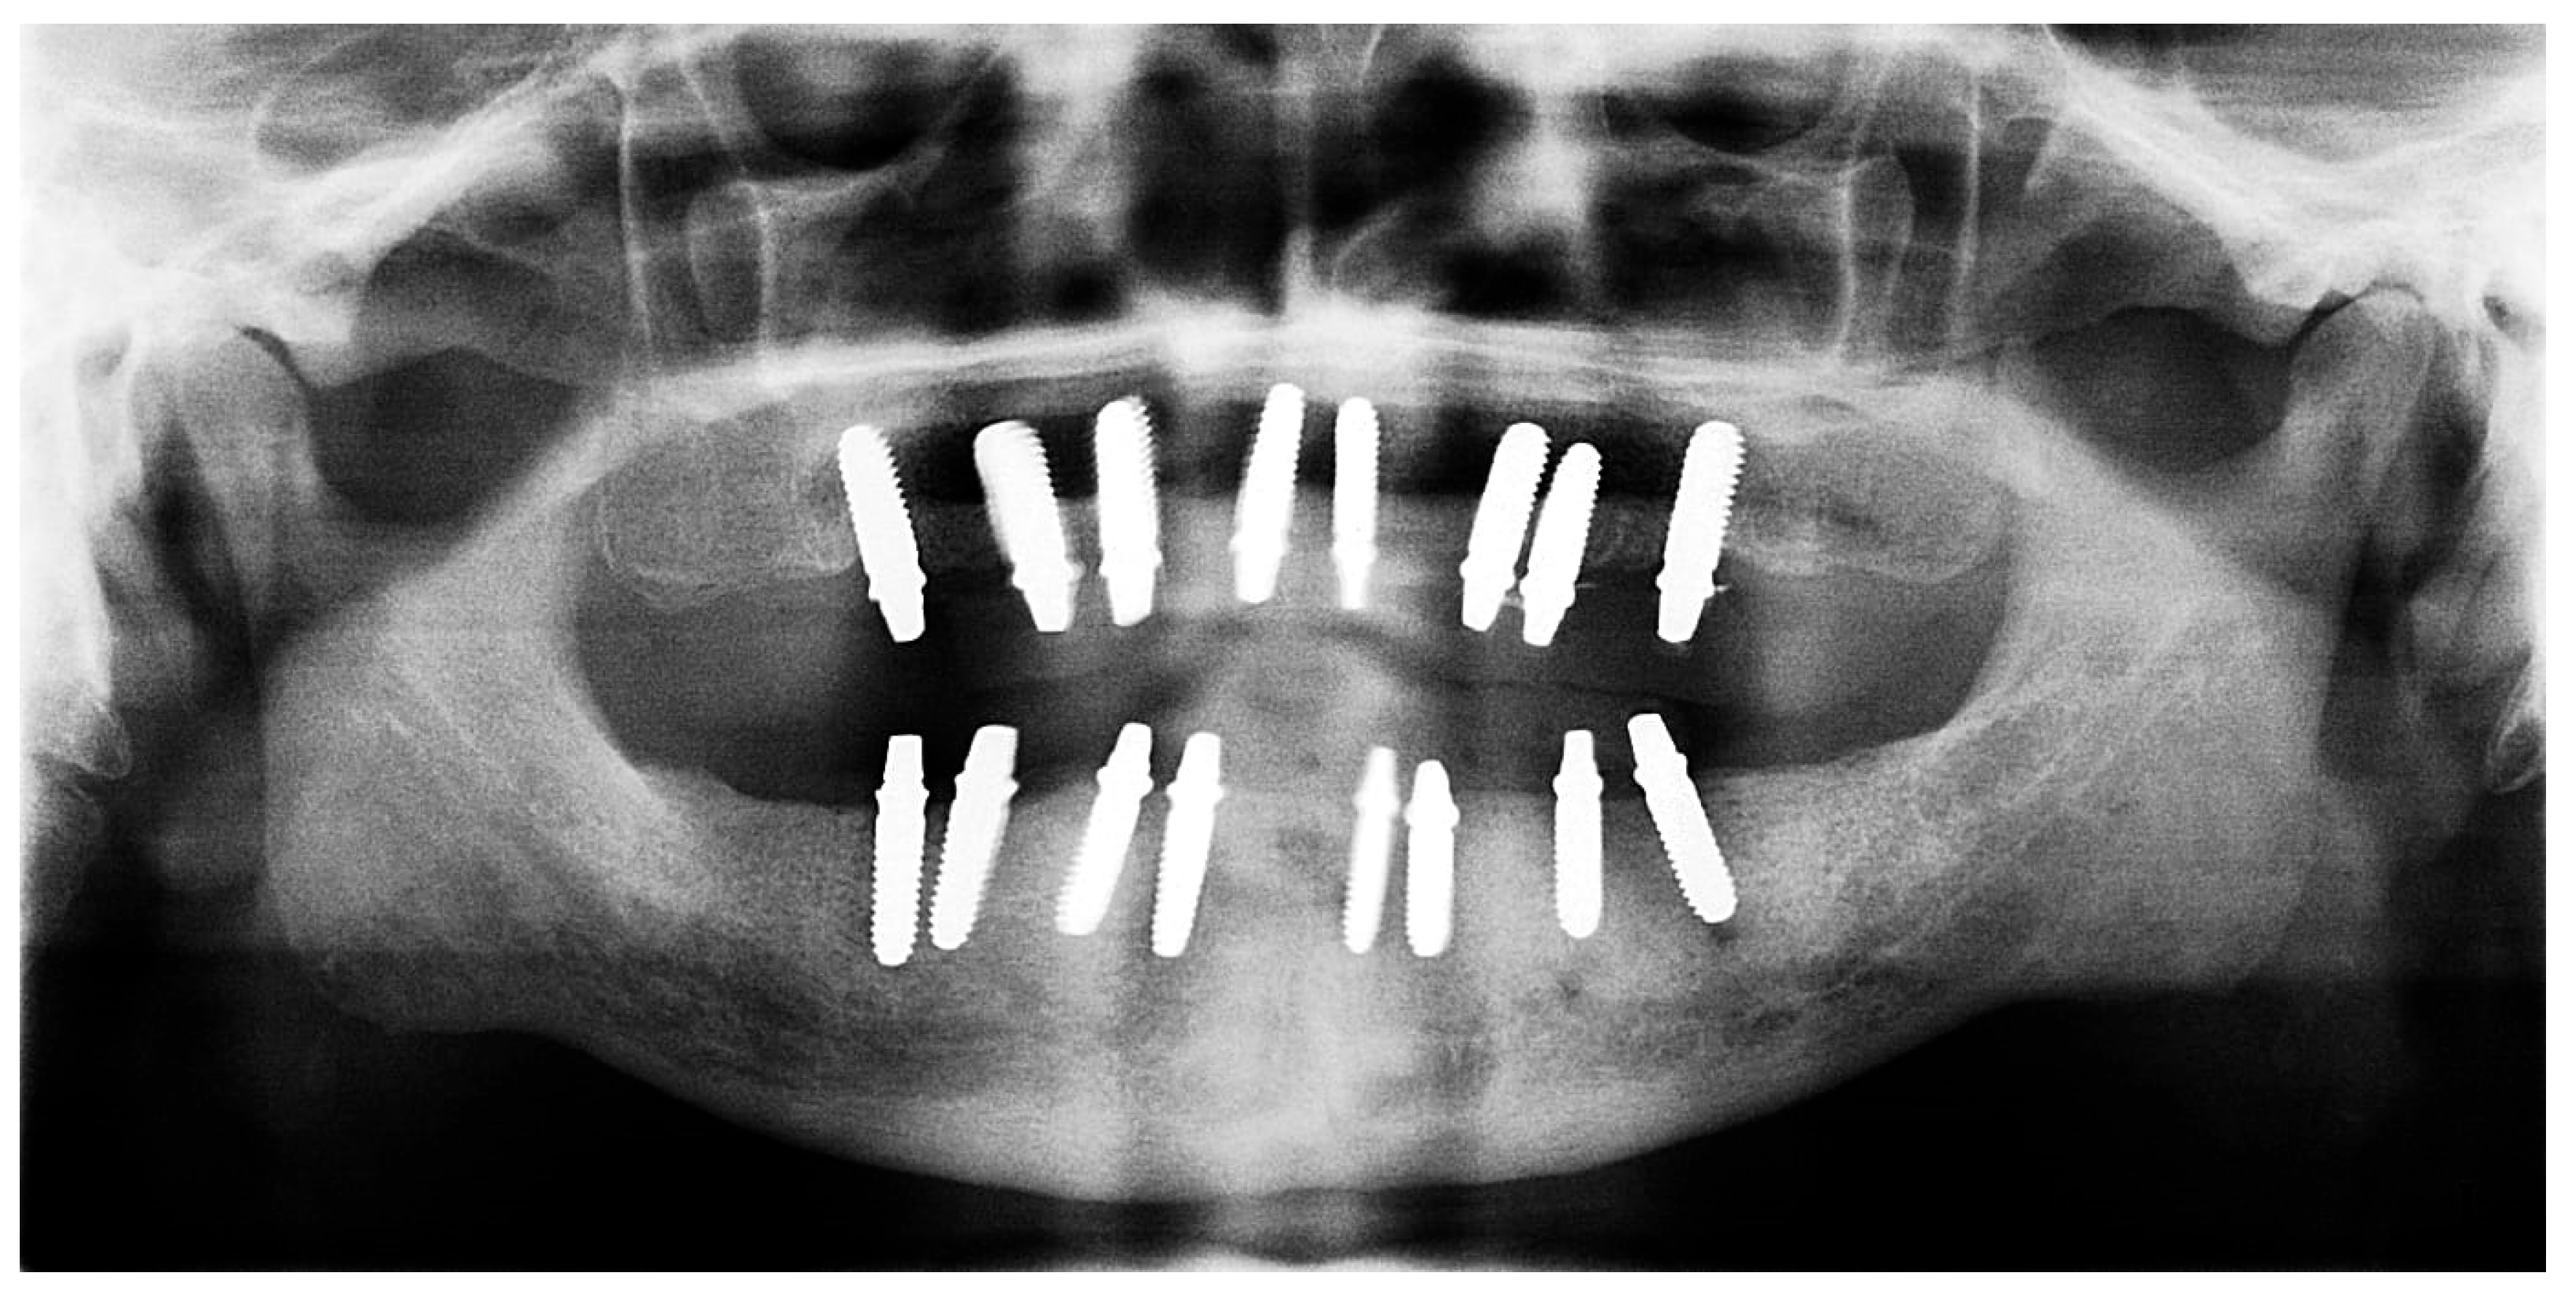

2.5. Fifth Visit

The restoration plan involved placing a bridge that connects the central incisors to the canines, along with an additional bridge spanning the first premolar to the first molar on each side of the maxillary arch. In the mandibular arch, the plan included three bridges: one connecting the lateral incisors bilaterally and another bridging the canines to the second premolars and first molars on each side (Figure 14 and Figure 15). Placing was confirmed using Panoramic radiographs obtained using the PantOs DG XP panoramic dental X-ray system (Fona S.r.l., Assago, Italy; CE 0051). The unit operates on a 230 V, 50/60 Hz input line with an 8 A fuse. Standard panoramic exposure parameters were applied (90 kVp, 10 mA, exposure time 14 s) following the manufacturer’s safety recommendations. A trained radiology technician performed all scans, and patient positioning was standardized using the built-in cephalostat support and light-beam alignment to ensure reproducibility of serial images.

Figure 13. Panoramic X-ray showing the inserted dental implants (taken 10 October 2022).

Figure 15. Panoramic X-ray showing the final prostheses (taken 21 November 2023).